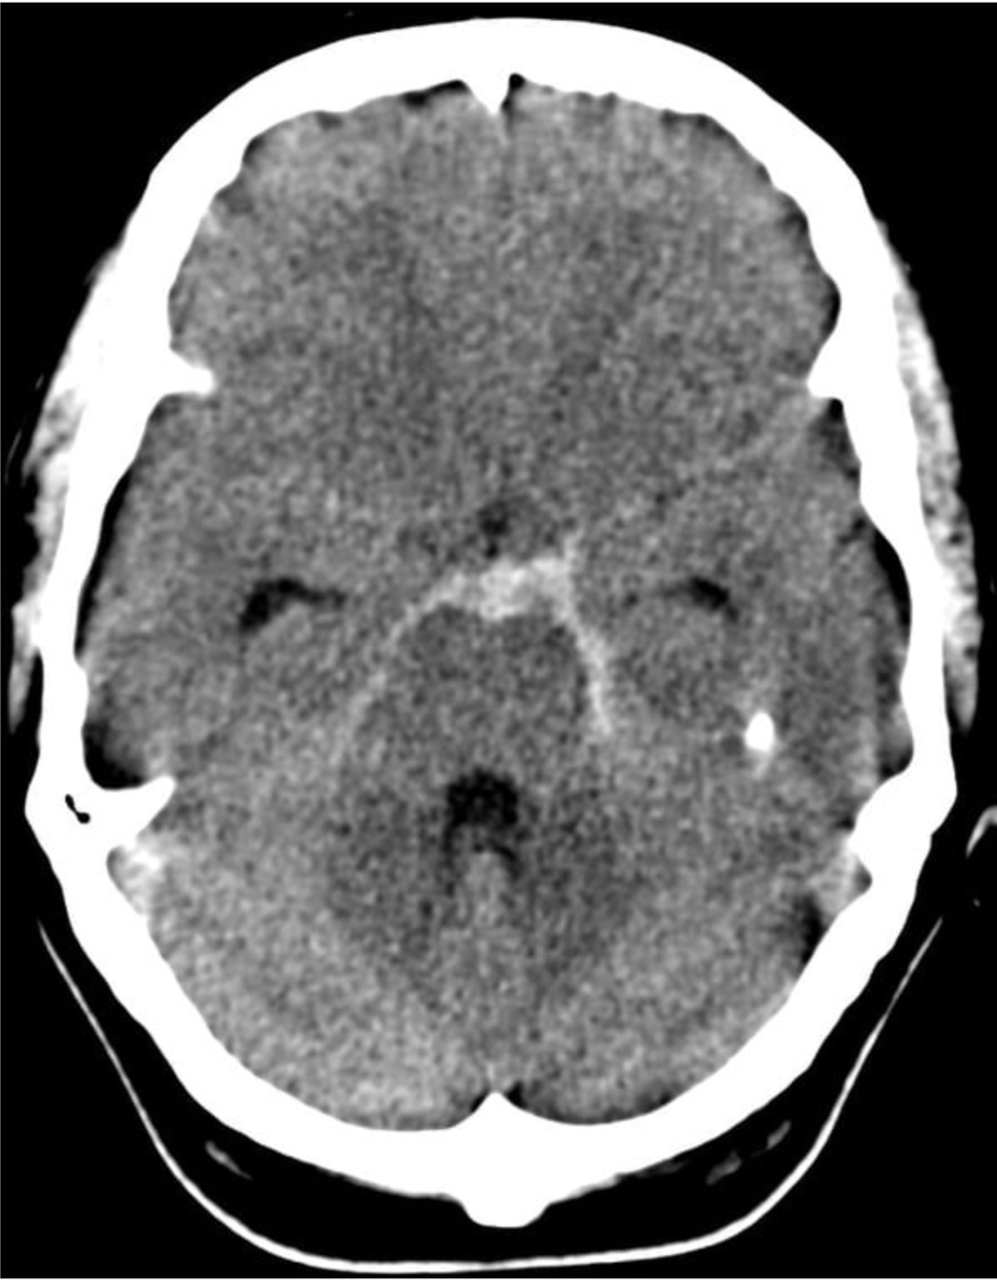

L’hémorragie sous-arachnoïdienne (HSA) a une symptomatologie qui est très importante à connaître, pour les ECNi comme pour la pratique. On retrouve une céphalée BRUTALE, d’emblée maximale (une heure précise d’arrivée est un signe évocateur).